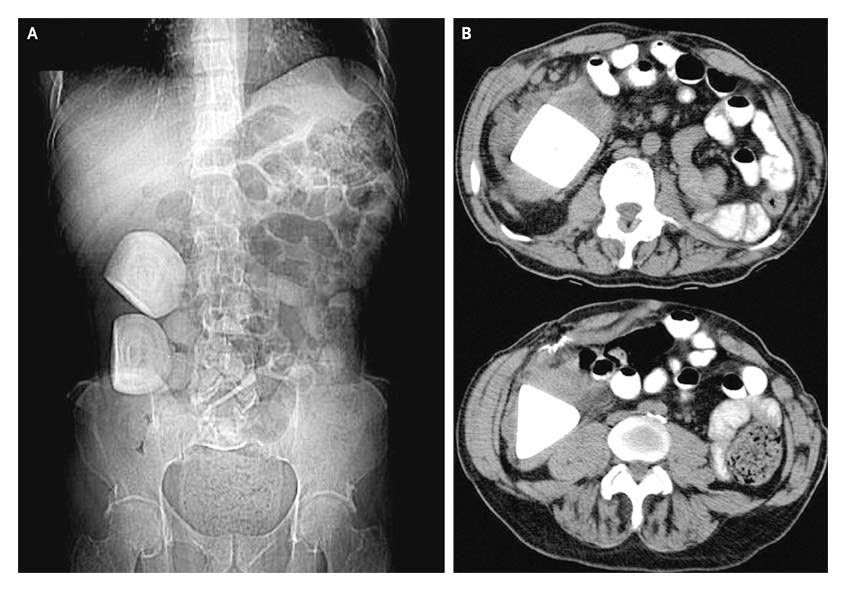

From doctorsgates.blogspot.com

Doctors Gates Calcifications in a Continent Urinary Diversion Indiana Pouch Irrigation An indiana pouch will be the new storage area for. Creating a continent catheterizable pouch, an ileal conduit, or a neobladder. An indiana pouch is a type of urinary diversion. It is essential, while the pouch is learning to grow, that catheterization occurs by the clock. There are three main ways to divert the flow of urine away from the. Indiana Pouch Irrigation.